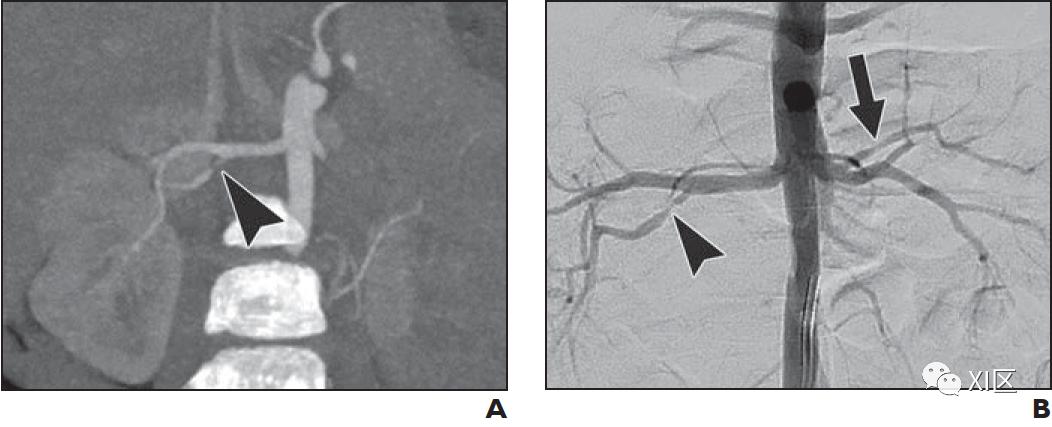

肾血管疾病的CTA表现包括动脉不规则,串珠样轮廓和狭窄(图9)。儿童的大多数肾动脉狭窄累及主要,附属或节段性肾动脉。在CTA上很难显示二级分支远端的实质内动脉,而DSA可能对于明确排除肾脏实质内狭窄是必要的。狭窄的继发体征可能包括狭窄后扩张,侧支动脉的存在,局灶性实质性灌注缺陷,不对称的肾X线造影图和实质性瘢痕形成(图9)。

表2总结了常见的小儿中,大血管炎的详细描述。尽管DSA是血管炎的参考标准,但CT和MR血管造影可无创评估血管腔直径和炎性血管壁变化。大血管和中血管血管炎的影像学表现没有特异性,诊断需要临床标准。CTA可显示血管腔不规则或修剪,狭窄,动脉瘤或血栓形成(图10)。此外,应评估血管壁的同心或偏心增厚,增强,水肿或钙化(图10)。